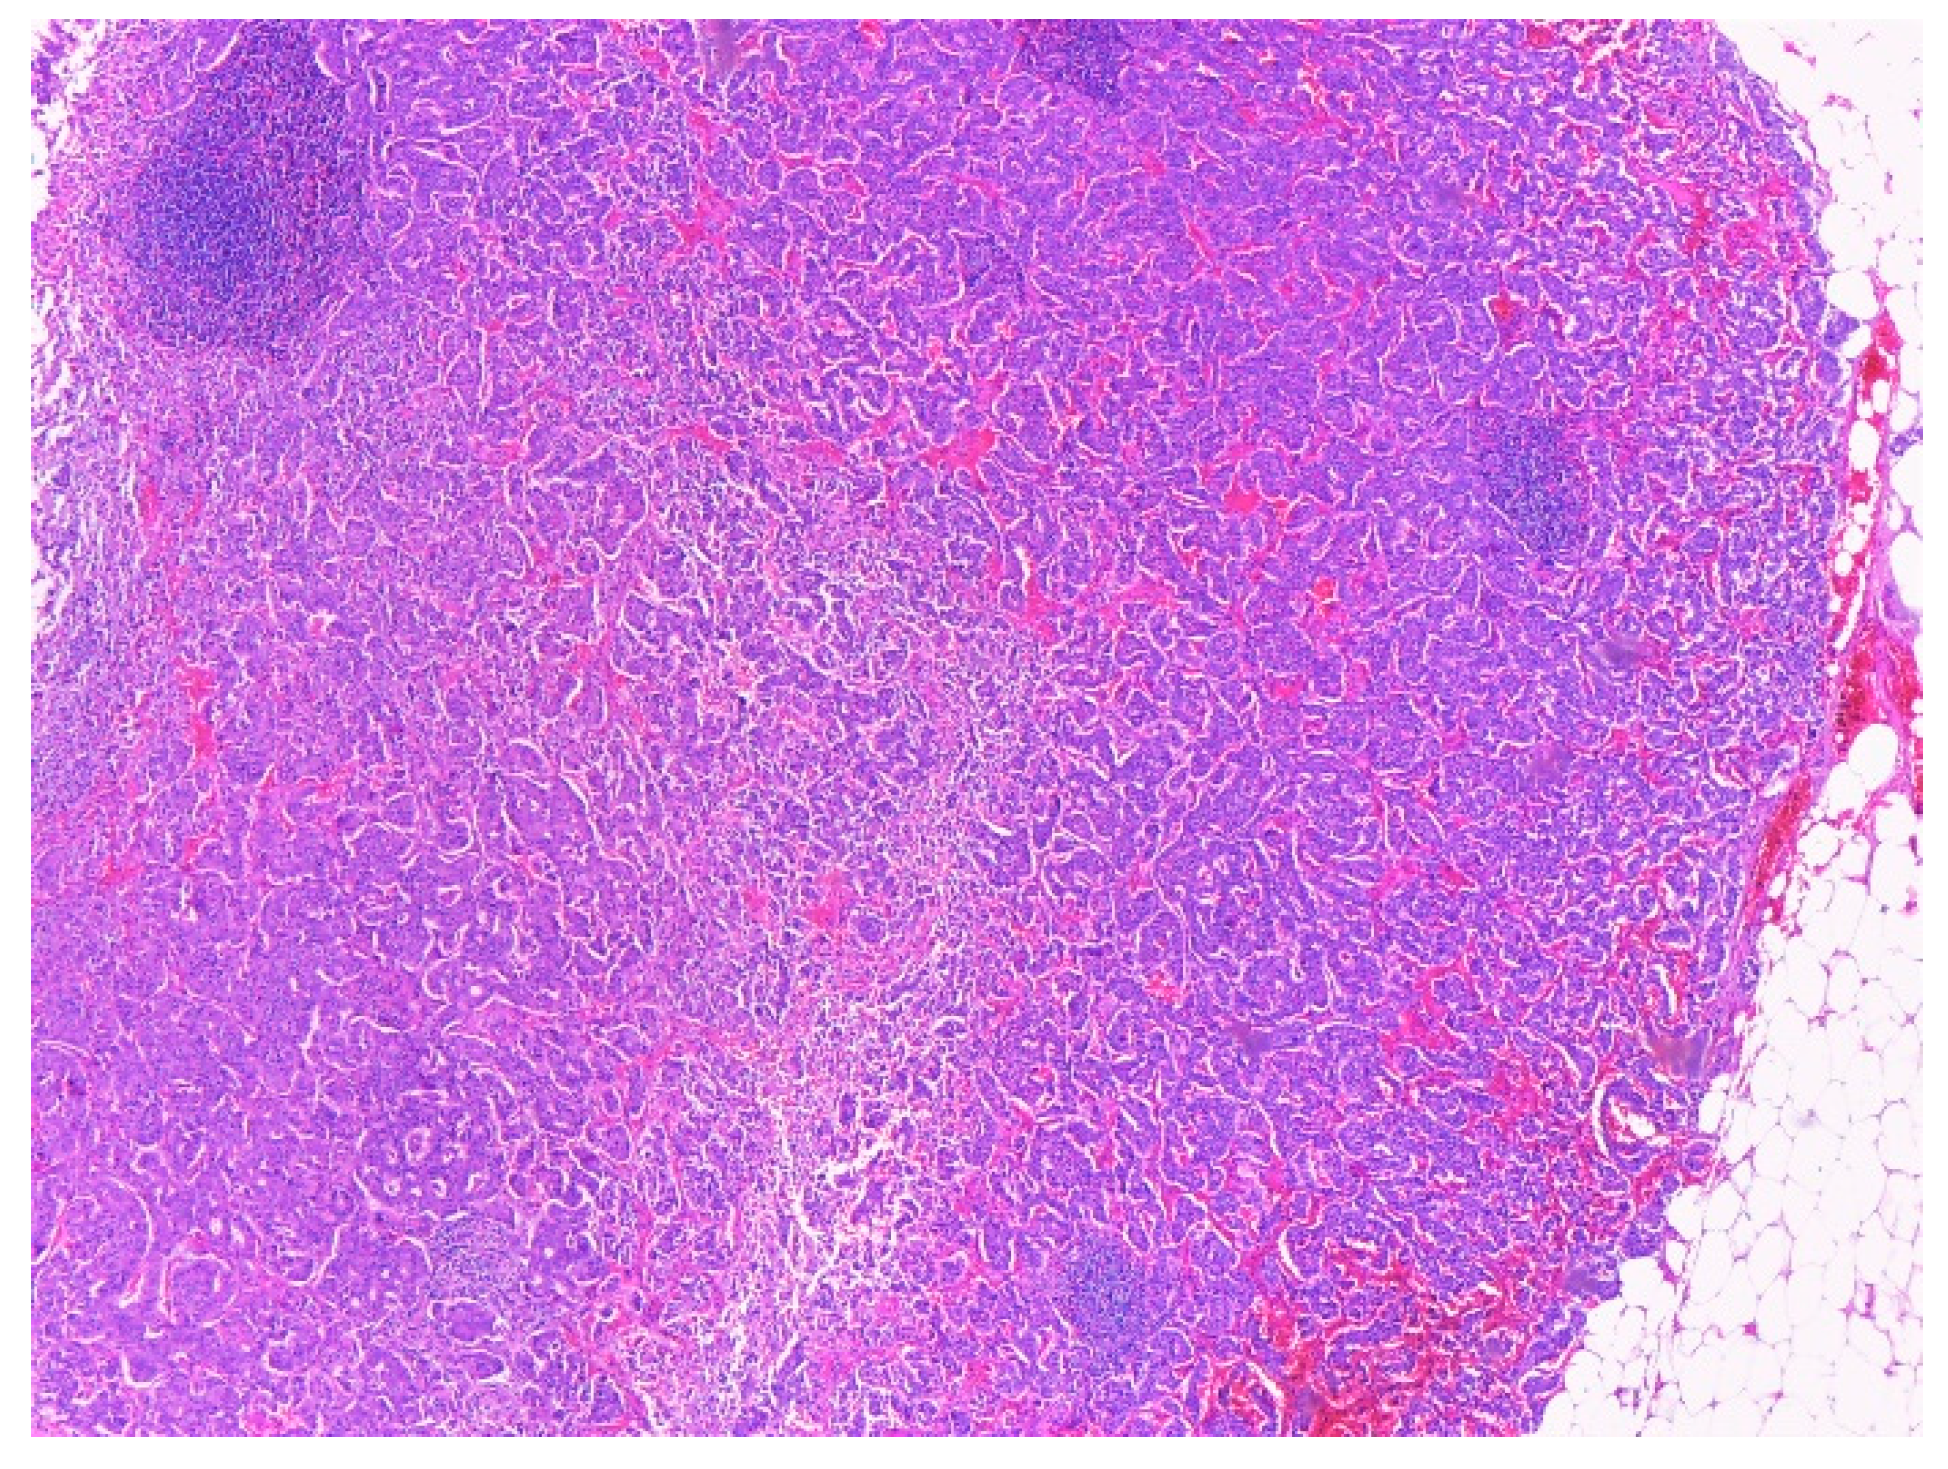

2.4. Histopathological Exam

| Aspect | Tumor proliferation with cells containing round, oval, pleomorphic nuclei, and fine granular chromatin. Proliferation covered the entire section and caused partial ulceration of the mucosa that crosses muscular propria layer and extends into the peripancreatic adipose tissue with discrete infiltration of pancreatic acini. Infiltration was clearer after synaptophysin labeling. | Tumor proliferation with atypical cells, fasciculate disposition, elongated nuclei, discrete nucleoli, and pale eosinophilic cytoplasm. The apparent origin of the tumor is muscularis propria | Small intestine sample with tumor proliferation, composed of cells with fascicular disposition, elongated and non- pleomorphic nuclei, pale eosinophilic cytoplasm, rare epithelioid cells. The apparent origin of the tumor is muscularis propria | Sample muscle proliferation with tumor proliferation composed of cells without atypia, fascicular disposition, elongated nuclei, discrete nuclei, and pale eosinophilic cytoplasm | Sample muscle proliferation with tumor proliferation composed of cells without atypia, fascicular disposition, elongated nuclei, discrete nuclei, and pale eosinophilic cytoplasm |

| Tumor cells | CgA-positive SPY-positive Ki67-reduced, maximum 2% | c-kit-positive DOG1 positive SMA-negative | c-kit-positive DOG1 positive SMA-negative CgA-negative | c-kit-positive SMA-negative | c-kit-positive SMA-negative |